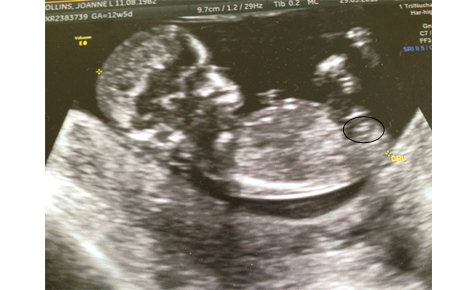

Ok so I have posted before and this is truly driving me crazy. I have 40 scan pics altogether and am constantly looking through them. So just now I have come across something which I would like to get your opinions on please. Ok so I'll post some pics now and explain what I'm wondering. So this pic is the one that everyone has been guessing on and had some girl and some boys guesses - more recently more boy guesses. So my question is - Is the white line you can see actually the nub? The reason for me asking is please look at the 4d pic in the second pic below (this pic is taken within 1 minute of pic 1) - the cord is wrapped around the leg - around the leg on the side at which the profile pic is taken. So my question is - Could the white line at at the top actually be the cord as in pic 2 and the nub is actually the one i have circled in pic 3 posted below? Hope this makes sense and you get where I'm coming from :) Thanks for reading x

Pic 1

Attachment 11920